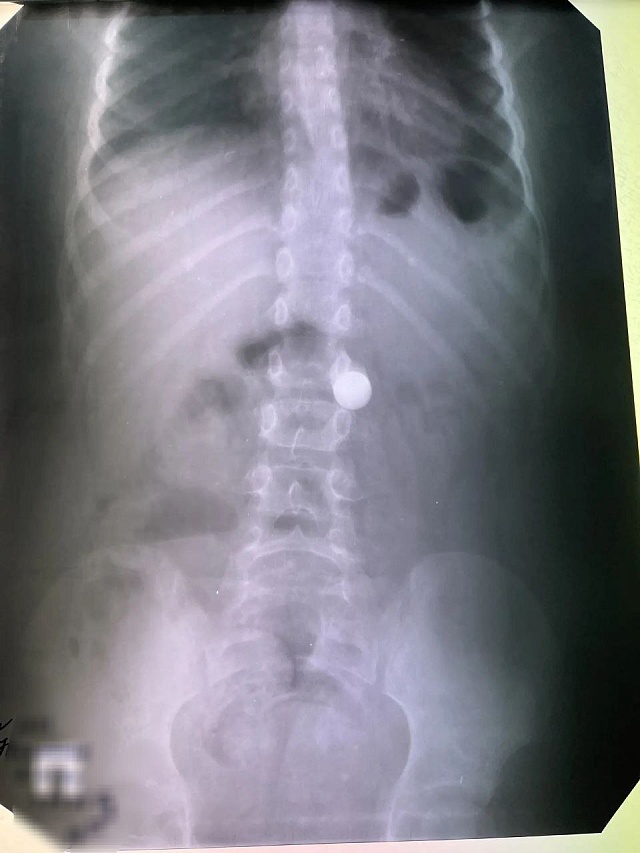

За весь период каникул поступил только один маленький "исследователь" — восьмилетний мальчик, который проглотил сантиметровый металлический шарик.

Фото: тг-к Балаковской городской клинической больницы